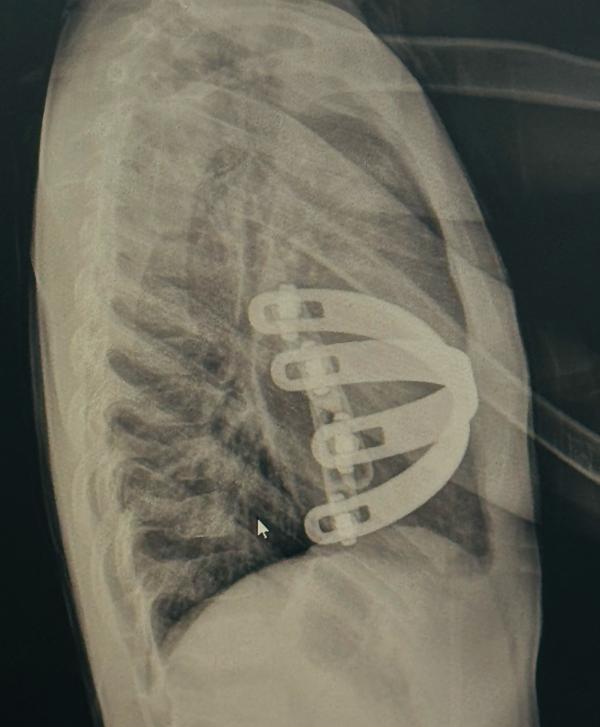

Severe “Grand Canyon” Type Pectus Excavatum – Complications and Surgical Correction

The Nuss Procedure: A Modern Solution for Pectus Excavatum in Chennai

The modified NUSS procedure is a minimally invasiv...